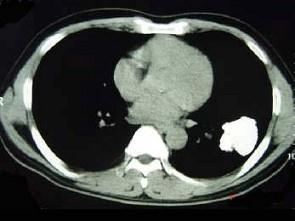

问题 男,45岁,体检发现左下肺占位,CT检查如图,最可能的诊断为 ( )

选项 A、左下肺炎性假瘤 B、左下肺感染 C、左下肺周围型肺癌伴钙化 D、左下肺错构瘤 E、左下肺结核球伴钙化

答案 D